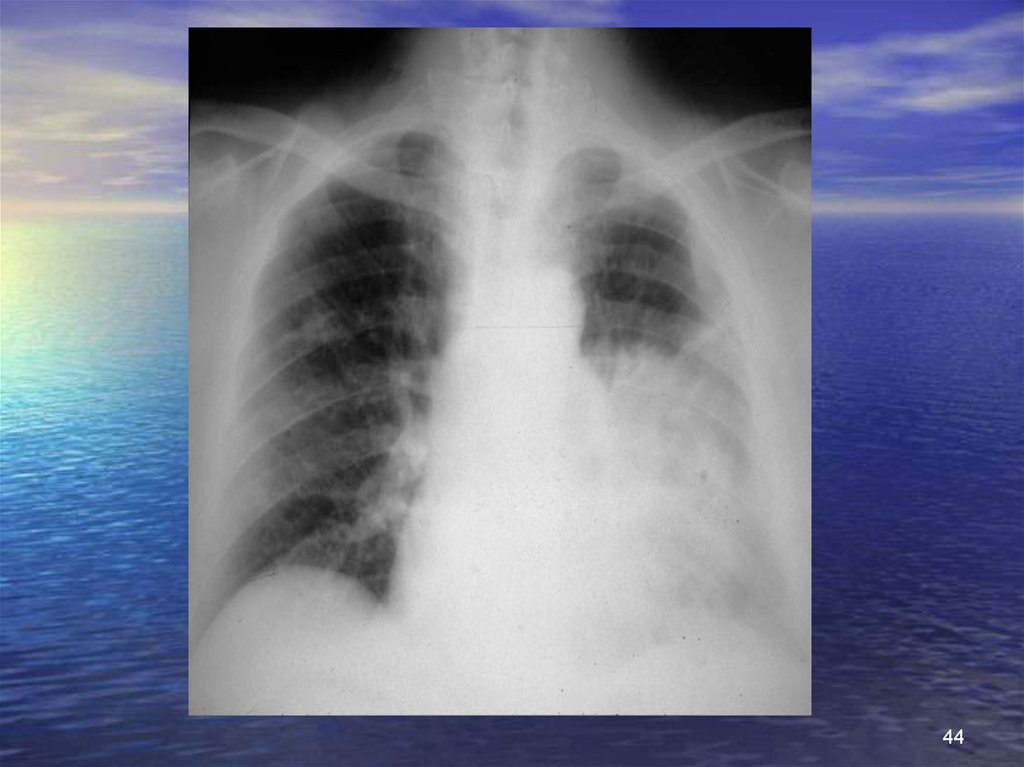

44.

44